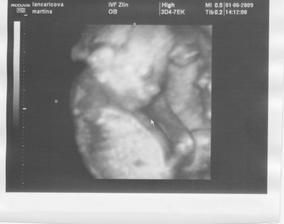

20.4.2009 dnes jsme byli i s manželem na prenatálním screeningu. Dopadli jsme výborně, malý měl všechny parametry v normě, nosní kůstka přítomna, srdíčko 155 tepů, pupečník i placenta krví zásobeny, žaludek...

Dokonce jsme slyšeli i první odhad pana doktora, co se týče pohlaví - ale věříme, že má pravdu, když mrknete do alba, tak jej uvidíte taky 🙂. Jednoduché to nebylo, museli jsme se jít projít a vypít čokoládu, prý na ni děti dobře reagují a skutečně - pak se nechal drobek změřit 🙂. Měří skoro 7cm, od minulé kontroly u paní doktorky před 10 dny vyrostl o 3cm - prý dobře vařím 🙂